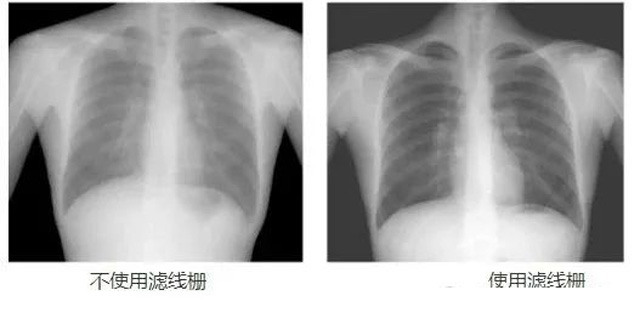

DR影像X射線在醫(yī)學(xué)檢查成像有著廣泛的使用。但是它的散射線影響成像質(zhì)量問題。濾線柵的發(fā)明使用很好的解決了這個問題,構(gòu)造簡單鉛條粗,密度和柵比規(guī)格單一,能減散射線但吸收較多原發(fā)射線。伴隨這醫(yī)療影像設(shè)備技術(shù)的發(fā)展,這個濾線柵的工藝制造技術(shù)有改進,鉛條變薄,柵密度和柵比有更多的選擇。特別是材料方面有新組合,填充物也依不同成像要求優(yōu)化。特別是移動DR這類型的DR設(shè)備的出現(xiàn),濾線柵也設(shè)計成立方便拆卸形的,方便使用。被照體情況決定是否使用,更好平衡成像質(zhì)量與射線劑量。

焦距(f):斷面看鉛條延長線會聚點到柵板垂直距離,即柵板焦距(半徑)。柵密度(N):每厘米范圍內(nèi)含有的鉛條數(shù),一般40~65線/cm。柵比(R):鉛條高度與柵條間隙之比,比值越高濾除散射線能力越強,一般8:1~14:1之間。結(jié)構(gòu)組成:3~5mm薄板,用0.05~0.1mm鉛條,夾持在鋁或紙之間平行或按斜率排列,相鄰鉛條間用易透X線物質(zhì)填充定位、黏合,如木、紙、鋁片等。

放置方面:置于人體與片盒間,聚焦面朝向X線入射方向,X線焦點放鉛條會聚線上,不能反置,X線中心對準(zhǔn)濾線柵中心,左右偏移不超3cm,傾斜X線管要與鉛條排列方向平行。攝影時焦距改變不超焦距的25%;活動式濾線器運動時間至少長于曝光時間的1/5;因吸收原發(fā)射線要適當(dāng)增加曝光條件;四肢薄位置一般不用濾線柵;不同千伏對應(yīng)不同柵比;立位胸片架、乳腺DR攝影等有各自特定濾線柵要求。